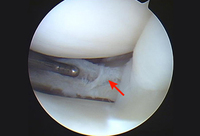

Arthroscopic view of suture repair of lateral meniscus (arrow)

From the collection of Dr Kevin R. Stone